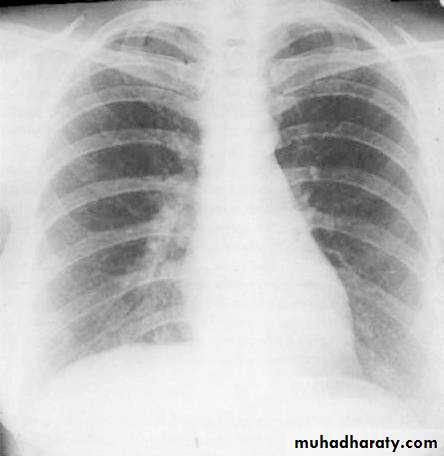

6) Good centering ( not rotated )

Both medial ends of clavicles are equi-distance from spinous process of adjacent vertebra .In rotated film , one side of the lung appear more opaque than the other with distortion of mediastinal borders.

Rotation .

Rotation of the radiograph is assessed by judging the position of the clavicle heads and the thoracic spinous process.7) Good technique (amount of radiation )